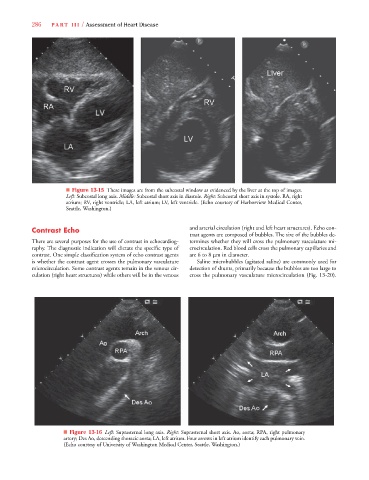

■ Figure 13-15 These images are from the subcostal window as evidenced by the liver at the top of images.

Left: Subcostal long axis. Middle: Subcostal short axis in diastole. Right: Subcostal short axis in systole. RA, right

atrium; RV, right ventricle; LA, left atrium; LV, left ventricle. (Echo courtesy of Harborview Medical Center,

Seattle, Washington.)

■ Figure 13-16 Left: Suprasternal long axis. Right: Suprasternal short axis. Ao, aorta; RPA, right pulmonary

artery; Des Ao, descending thoracic aorta; LA, left atrium. Four arrows in left atrium identify each pulmonary vein.

(Echo courtesy of University of Washington Medical Center, Seattle, Washington.)